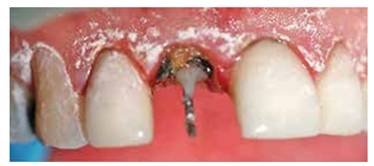

Se procede a remover la férula, corona y desobturar la pieza para colocar un alambre y poder realizar un muñón más estable para efectuar la extrusión ortodóntica. (Figuras 8A y 8B)

Figura 8A: Colocación temporal de alambre de ortodoncia de 0.9 mm de grosor, dentro del conducto y confección de muñón.

Figura 9:  Se colocan brackets y un alambre rectangular de 17 x 25 de nitinol con un doblés a nivel de 1.1 para realizar tracción coronal.